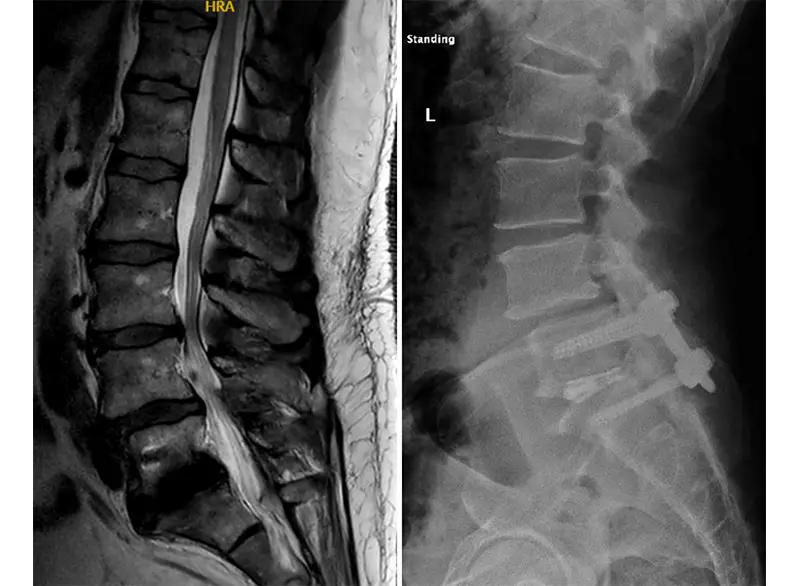

(Left) Post-operative MRI showing resolution of lumbar stenosis; (right) post-operative X-ray showing the spinal fusion at L5-S1 where the tumor has been removed.

After surgery, we got Bernard up and walking as soon as possible. He was released to recover at home one day post-operatively. With spine surgery, patients are encouraged to get up and moving as soon as possible. Walking is key to their recovery, and putting the responsibility on the patient to take the initiative to move is very helpful psychologically because it shows them that they can move. Two weeks after surgery, I encourage my patients to keep walking but also try to get into the pool, on the elliptical, or on a recumbent bike to continue their rehabilitation.